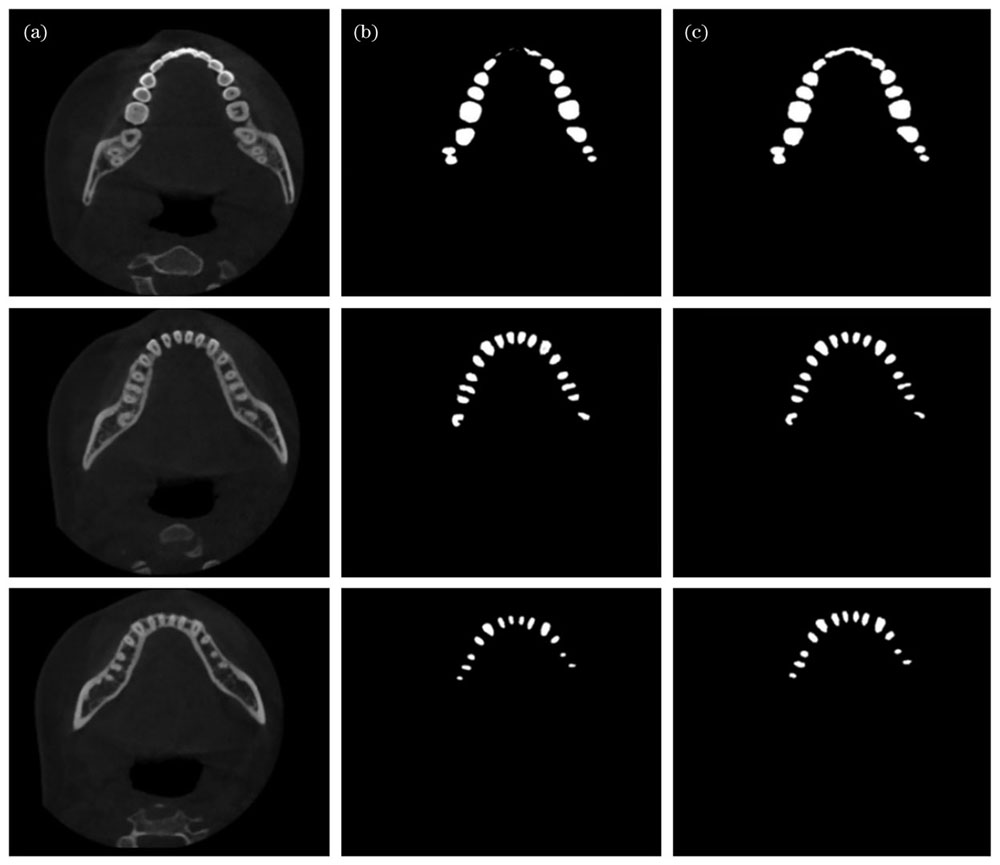

实际的牙齿分割识别效果如

图 7. U-net模型识别效果。(a)待识别图像;(b)原始U-net方法识别效果;(c)改进U-net方法识别效果

Fig. 7. Recognition results of U-net models. (a) Images to be recognized; (b) recognition results using original U-net model; (c) recognition results using improved U-net model

通过对比可以看出,相对于原始的U-net算法,本文算法识别效果更佳。对比两种算法对于第一幅图像的识别效果可见,由于局部亮度影响,原始U-net方法缺失了大量图形,而本文的改进算法仍能准确识别。对比另两幅图像的识别效果可见,在图像细节很少的情况下,本文算法识别出的图片中毛刺状伪影更少,证明了本文算法在牙根处也能进行有效识别。